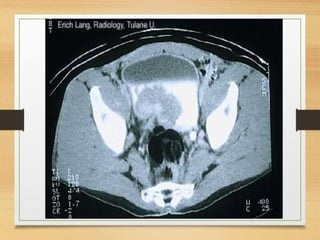

CASE 4

• A 64-year-old man presents with a 2-month history

of painless visible haematuria, hypertension, weight